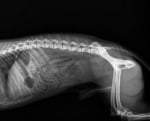

Рентгеновите лъчи дават подробна картина на вътрешната част на тялото на кучето. Те използват ниски нива на електромагнитни лъчения, за създаване на изображения на вътрешните органи, костите и зъбите.

Касетите биват най - различни форми в зависимост от зоната, която ще се облъчва с рентгенови лъчи. Рентгеновата техника се поставя неподвижно над целевата зона. Рентгеновите лъчи създават сиво-сенчести изображения на филма. Цветовете на филма се определят от плътността на тъканта и костите в целевата зона.

По - плътните области са по - бели. По - малко плътните области са светло сиви. Ако са необходими няколко рентгенови снимки, кучето трябва да бъде позиционирано по различни начини. Обикновено правенето на една рентгенова снимка трае от 5 до 10 минути. За да се получи пълната картина на снимката, трябва да се изчакат още 20-30 минути.